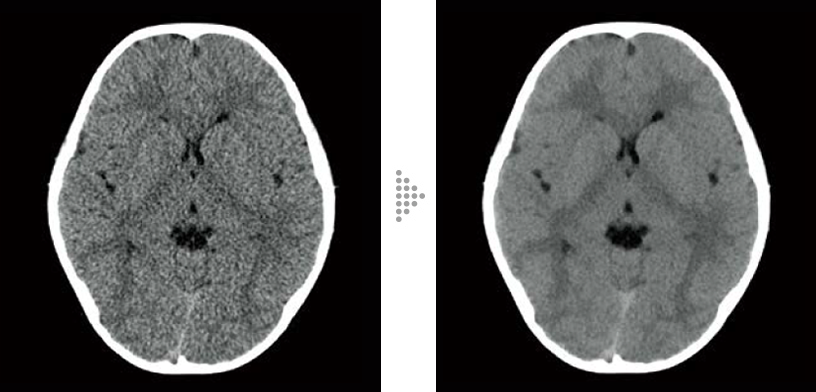

FBP(Left)

Intelli IPV(Right)

Brain tumor